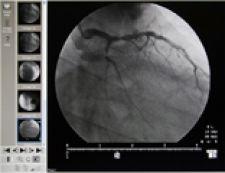

NovaRad’s NovaPACS Cardio Viewer offers sign-on access to images or over a website. Features included in this module include: image calibration based on catheter size, percent stenosis, choose series, cine tools, digital subtraction (displays contrast-filled vessels without any interfering background), ejection fraction and image-sharpening algorithms.

Images from the system are stored an Online RAID 5 Archive designed with the capacity to display multiple cardiac images simultaneously and access to patient’s entire radiological or cardiological history.

NovaPACS Cardio Viewer is available as a standalone model or can be added to an existing NovaRad Enterprise workstation.